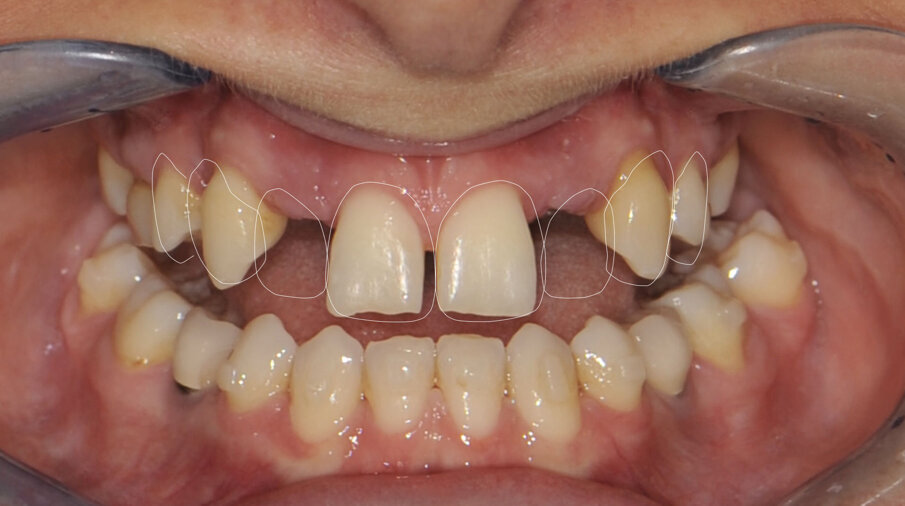

Om de behandeling niet nodeloos ingewikkeld te maken, is een set-up gemaakt waarin is gekeken of we met een restauratief/orthodontisch behandelplan uit de voeten kunnen om zo orthognatische chirurgie te vermijden. Er werd een wax-up gemaakt en deze werd met Luxatemp gepast bij de patiënte om te beoordelen of we dimensionaal goed zouden uitkomen. Deze mock-up werd ook gemaakt om patiënte te laten zien welk uiteindelijk esthetisch resultaat we zouden kunnen benaderen (afbeelding 3 en 4).

In samenspraak met de patiënte en in goed overleg met de behandelend orthodontist werd besloten de implantaten op de posities 13 en 23 te verwijderen, de cuspidaten naar distaal te verplaatsen en de angulatie van de elementen te corrigeren, zodat het plaatsen van twee implantaten op de posities van de laterale incisieven goed mogelijk zou worden (afbeelding 5 en 6).